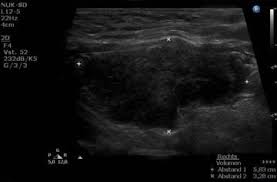

Diagnose Der Hashimoto Thyreoiditis Was Gilt Es Zu Beachten Hashimoto Info De

Wie Wird Die Diagnose Hashimoto Thyreoiditis Gestellt Dr Lunow Hashimoto Blog